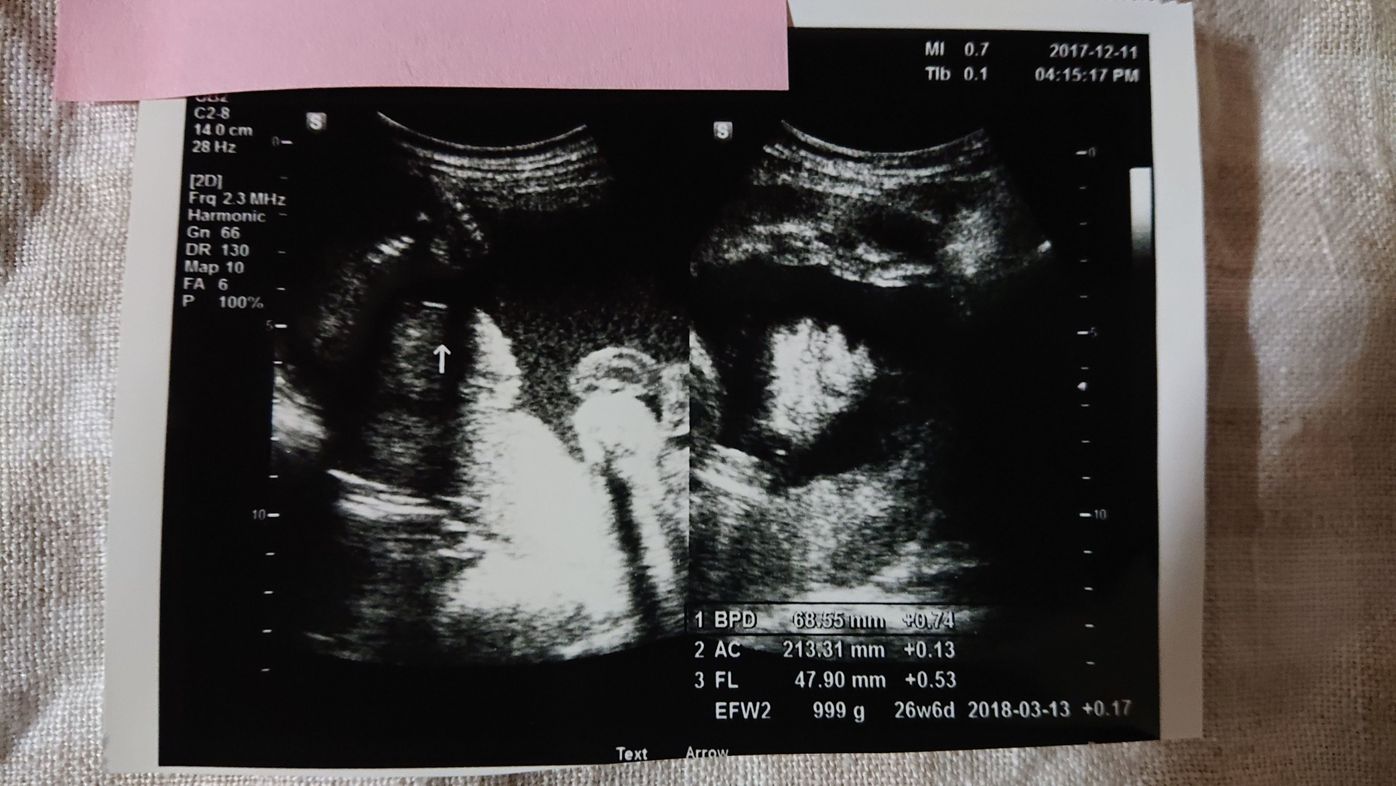

性別確定 こんばんは 妊娠中で26週になり女の子確定と言われました 避妊 教えて Goo